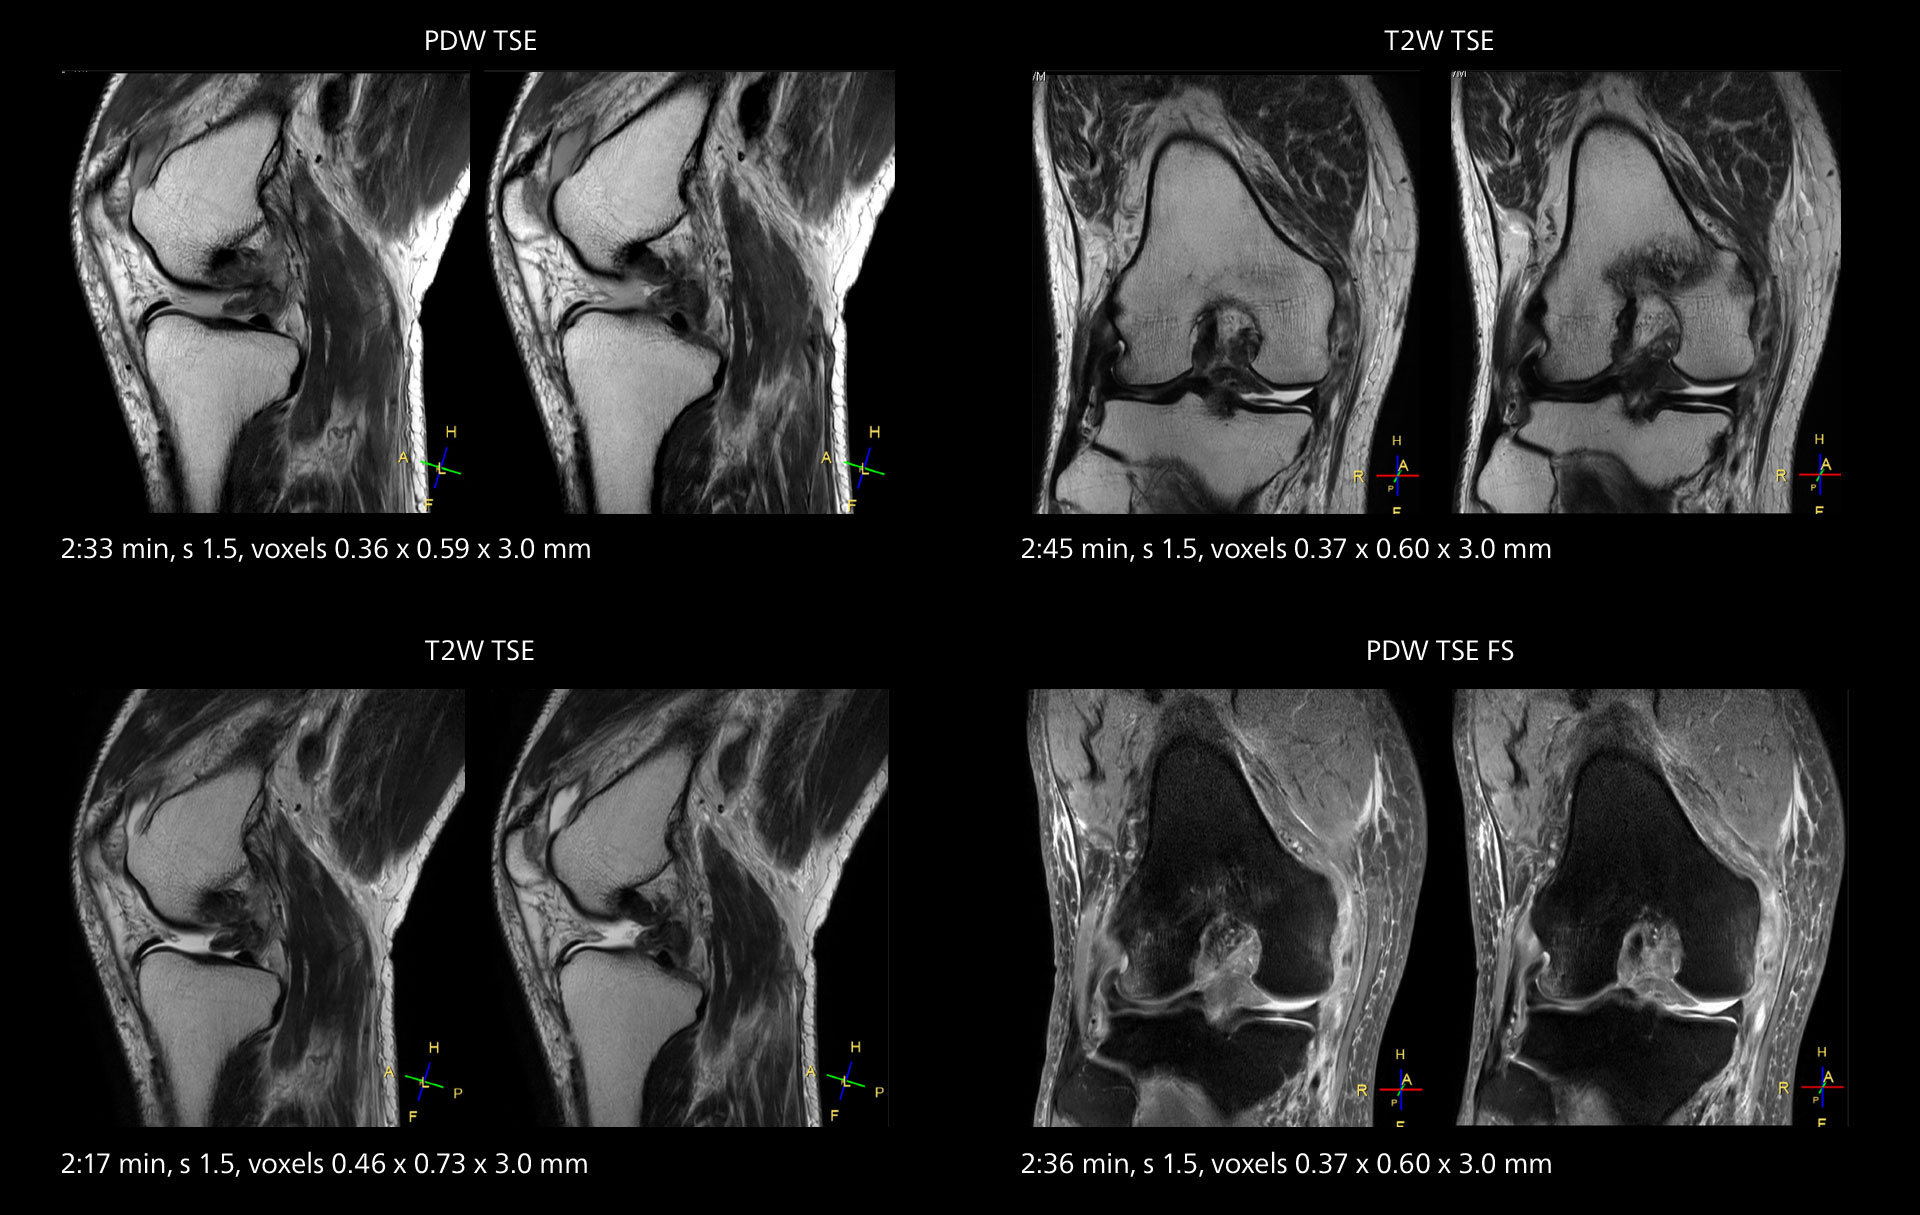

MRI of the knee

Images showing a posterior cruciate ligament (PCL) tear, a detached medial collateral ligament (MCL) on the tibial side and an intact anterior cruciate ligament (ACL). SmartPath to Elition X helped reduce scan time compared to previous imaging while maintaining resolution.

An example of increased imaging speed is in knee studies. “There is a definite scan time reduction for T2* mFFE and proton density TSE – both of these sequences benefit from much shorter repetition times,” he reports.

Overall, imaging time per sequence has been reduced since the Elition X upgrade. This can help reduce the risk of patient movement and the need for rescans.